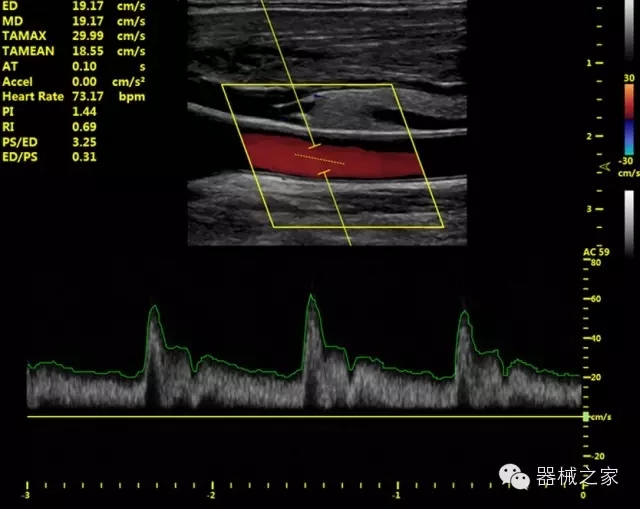

臨床圖片賞析

產(chǎn)品特點(diǎn)

·獨(dú)有的HoloTM PW 實(shí)時(shí)3取樣門PW成像技術(shù),精確進(jìn)行血管診斷;

·一鍵優(yōu)化B、Color、PW,Auto Doppler自動(dòng)識別血管位置、偏轉(zhuǎn)角度等,提高工作效率;

·30°超廣角精細(xì)偏轉(zhuǎn)成像技術(shù),更優(yōu)異的頻譜圖像;

·W+智能搜索引擎,快速尋找圖像;

·SSD、USB3.0保障開機(jī)快,導(dǎo)出圖像更快,減少等待時(shí)間;

·WIFI、網(wǎng)口、3G,多重聯(lián)網(wǎng)方式,全天候保障云端備份,不再擔(dān)心圖像丟失;